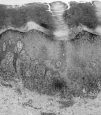

El estudio histopatológico de una de las lesiones palmares (Fig. 2) mostró una epidermis acantósica irregular «en dientes de sierra», con hiperqueratosis ortoqueratósica e hipergranulosis focal. En la dermis papilar había un denso infiltrado linfocitario en banda, bien demarcado en su límite inferior y que contactaba con la capa basal en su porción superior; ésta mostraba una degeneración licuefactiva con formación de hendiduras entre epidermis y dermis y presencia de cuerpos coloides de Civatte. Todos estos hallazgos confirmaron que se trataba de un liquen plano.

FIG. 2.--Imagen histopatológica típica de un liquen plano (HE, *40).